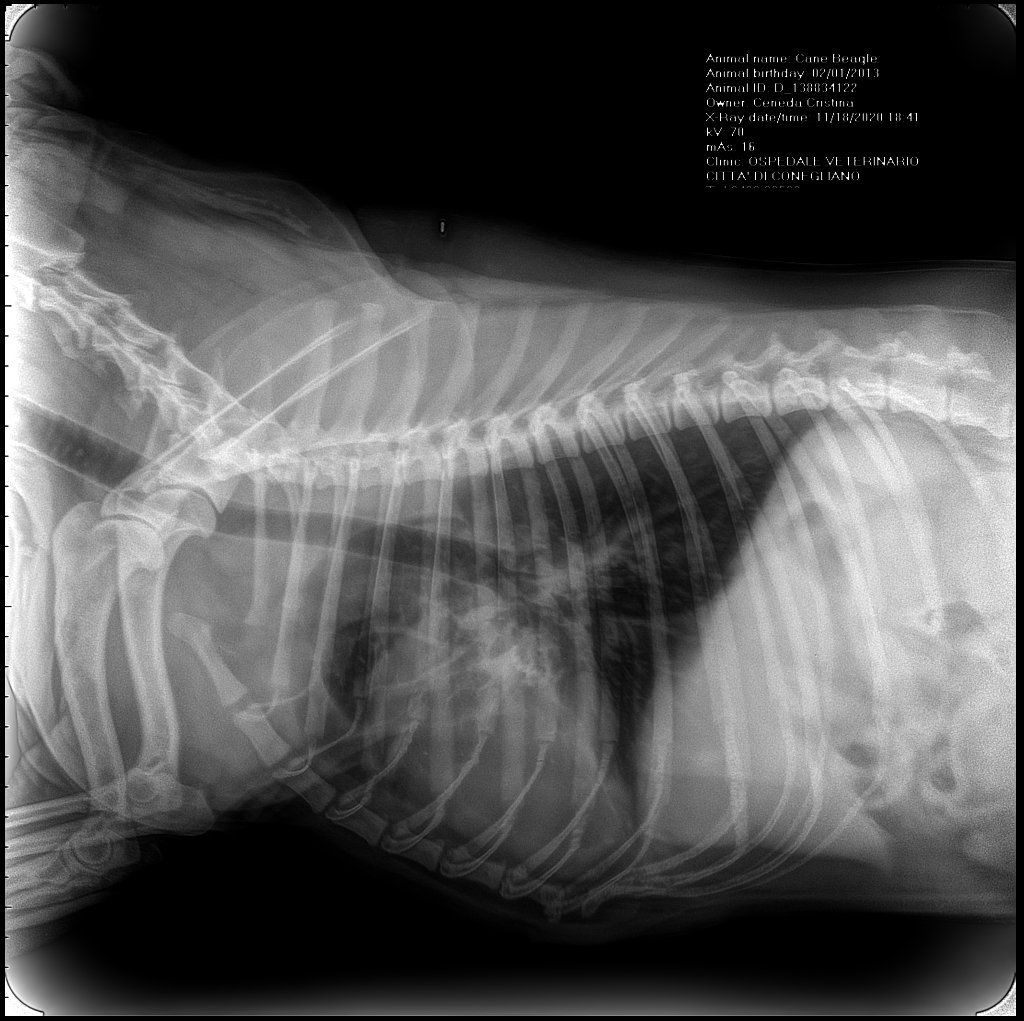

Diagnostica per immagini

Tra i servizi che l’Ospedale Veterinario Città di Conegliano fornisce, non mancano quelli di diagnostica per immagini:

ecografia, radiologia digitale, TC.

Gli specialisti Roberto De Pellegrin e Riccardo Pelizzon, in particolare, si occupano degli esami ecografici, ecocardiografici, tomografici per l'acquisizione di immagini del corpo del paziente attraverso l'esposizione a ultrasuoni o a raggi X.

Si tratta di esami non invasivi né dolorosi, che possono essere eseguiti molto rapidamente.